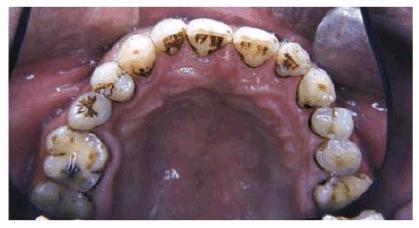

Figure 16-2A and B: Total neglect resulted in severe staining

of this patient's teeth.